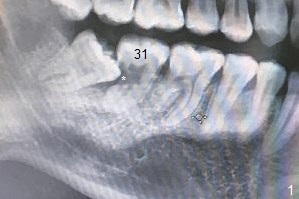

Subgingival Caries of 2nd Lower Molar

A 29-year-old woman has severe toothache associated with #31 subgingival caries (Fig.1 *). The affected tooth will be extracted prior to #32. Pointed/Lindamann bur with 4 mm stopper will be used to initiate osteotomy in the mesial socket of #31. Following 2.2 mm drill with the same stopper, insert marked parallel pin for PA. While Osteogen plug is going to be used to pack #32 socket and 31 distal socket (apical half), Vanilla graft with Osteogen will be used to fill the coronal portion of #31 socket. Suture may be used to close #32 socket if the immediate provisional at #31 fails to do so. In fact, no immediate implant is placed. The tooth: 32 socket receives a piece of 10x20 mm OsteoGen Plug, while #31 one Vanilla Cancellous/Cortical Mix with Osteogen (Fig.2 *), covered with Osteogen plug, 4-0 Chromic gut suture (figure-8 and interrupted), 2x2 gauze, hemastatic. The sockets heal nearly 5 months postop before the patient returns to her home country for living.